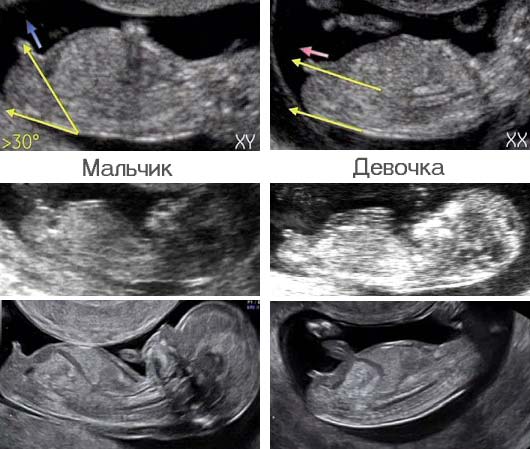

Девочка или мальчик?

Вопросы про УЗИ, обследования и анализы: что, где, как, когда?Девочки, кто разбирается, скажите кто?)) видно что - то! На узи предположили мальчика!

Мне кажется, что как у девочки торчит, у мальчика вверх сильнее. Но не очень пока понятно. У нас сразу было ясно

На первом скрининге половой бугорок торчит у всех. У меня у девочки торчал почти параллельно телу, у мальчика ровно вертикально. Тут я думаю скорее мальчик)